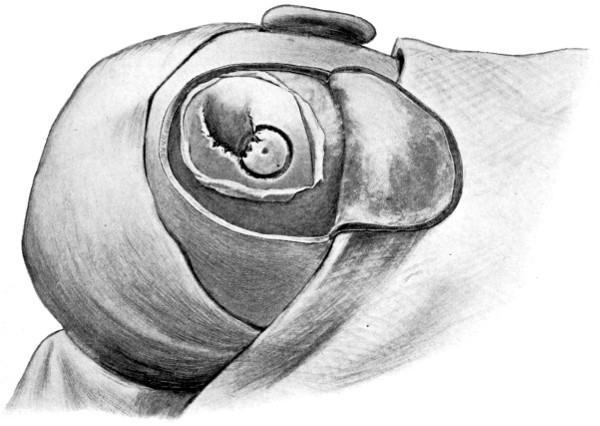

Fig. 20. An Occipital Cephalocele. (For further description, see text.)

1. Occipital cephaloceles—the commonest variety—occupy, anatomically, two positions (1) between the two lower segments of the occipital bone (inferior occipital cephaloceles), often involving the foramen magnum and sometimes complicated by a condition of cervical spina bifida, and (2) between the two upper segments of the occipital bone (superior occipital cephaloceles), occasionally involving the posterior fontanelle.

The tumour may possess a broad base or may be definitely pedunculated. In the former instance the gap in the bone may be of considerable size and the margins everted: in the latter case, the hole may be quite small.

The deformity is frequently associated with other congenital defects—hydrocephalus, microcephalus, spina bifida, hare lip, hernia, and talipes.

Sincipital cephaloceles are usually quite small, but the occipital variety and those situated in[35] the region of the anterior fontanelle frequently attain a great size (see Figs. 20-22).

Fig. 22. An Occipital Cephalocele. (For further description, see text.)

The child was 3 months old, and presented a tumour, the size of an orange, situated between the occipital protuberance and the nape of the neck. The mass was pedunculated, the stalk being about the size of a four-shilling piece in diameter. It was soft, translucent, irreducible, and swelled up on coughing. An attempt at removal was carried out, and, after incising the outermost layers, three ounces of cerebro-spinal fluid escaped. A second tumour was then found occupying the base of the swelling. This was also punctured, more fluid escaping. Both sacs were cut away and the wound sewn up. Death occurred on the third day, preceded by convulsions, retraction of the head and neck, and high fever. The autopsy showed that the fontanelles were widely open, the anterior measuring 4 inches from side to side and 21⁄2 from before backwards. The bones of the vault were markedly thinned. In the subdural space there was a quantity of fluid, and the cerebral substance was soft and diffluent, the convolutions flattened, and the ventricles distended. There was a broad gap in the occipital bone, extending downwards into the foramen magnum, and in this situation the cerebellum had bulged backwards into the protruding mass. (See Fig. 22).